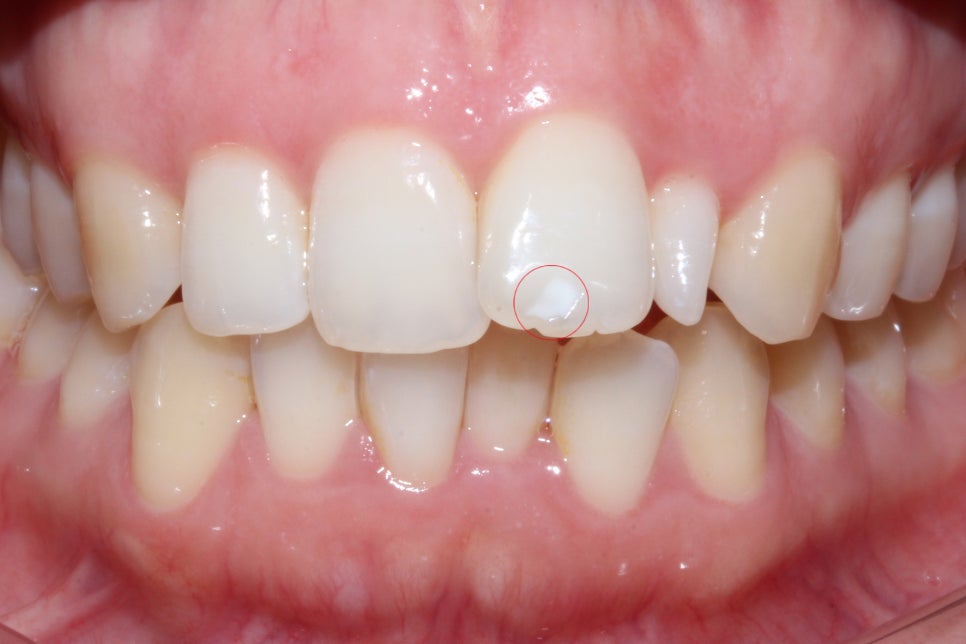

왜소치 외에도 상악 왼쪽 중절치의 표면에

흰 반점이 있는 반상치 증상이 나타나기 때문에

이 부분은 추후 치아색과 비슷한 resin으로

보완하여야 하는데요, 이러한 반상치 증상이

부분적으로 나타나는 것이 아닌 치아 표면에

전체적으로 발생하여 resin 치료가 불가능한 경우

무삭제 라미네이트 '세라필름'을 부착하여

치아의 표면을 매끈하고 균일하게 보완할 수 있습니다.

뻐드렁니 교정 후 중절치의 탈회 부분을 보시면

치아색과 차이가 없는 비슷한 색상의 레진으로

커버된 것을 확인할 수 있는데요,

보다 효과적이고 장기적인 유지를 원하실 경우

레진보다 영구적인 세라필름으로 치아를

수복하시는 것도 좋습니다.